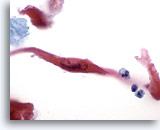

画像 2

肺FNA、肺大細胞癌明瞭な細胞縁を呈するシート状低分化癌細胞。細胞は統制されておらず、局所的に核の重積が見られます。背景には何も見られず、腫瘍性背景を呈していません。腫瘍細胞には、扁平上皮ないし腺管への分化に特異的な特徴は認められません。

40倍

画像 2

肺FNA、肺大細胞癌

明瞭な細胞縁を呈するシート状低分化癌細胞。細胞は統制されておらず、局所的に核の重積が見られます。背景には何も見られず、腫瘍性背景を呈していません。腫瘍細胞には、扁平上皮ないし腺管への分化に特異的な特徴は認められません。

40倍